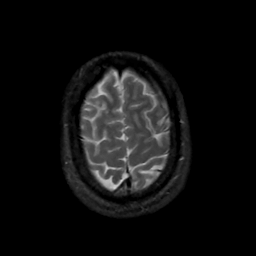

MR Study #14, June 2, 1991 -- Slice #43

[Home][Help][Clinical][Tour 1][Tour 2] Slice 43